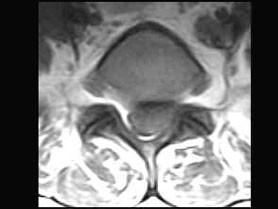

问题 男,50岁,有腰腿疼痛2个月,疼痛可向左下肢放射,请结合所提供图像,选出最佳选项 ( )

选项 A、L/S椎间盘膨出 B、L/L椎间盘膨出 C、L/L椎间盘突出 D、椎间盘变性 E、L/S椎间盘突出

答案 E